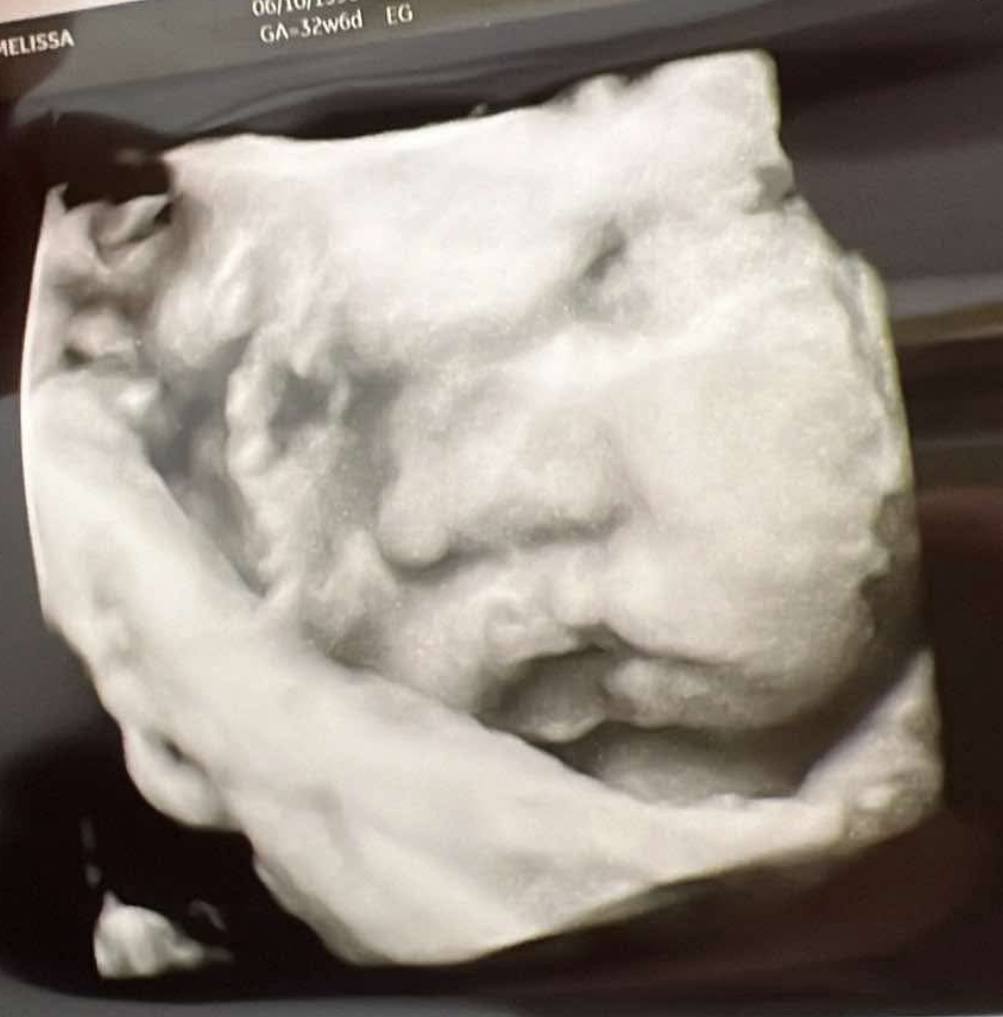

Athena Margaux was born on January 29, 2025, and passed peacefully five days later.

Though her time with us was short, her impact is eternal. In her tiny presence, she showed us the meaning of unconditional love, sacred grief, and the urgent need for compassionate care for grieving families.